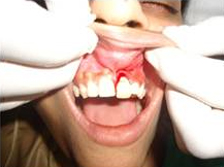

Pre Operation

Single Tooth Implant